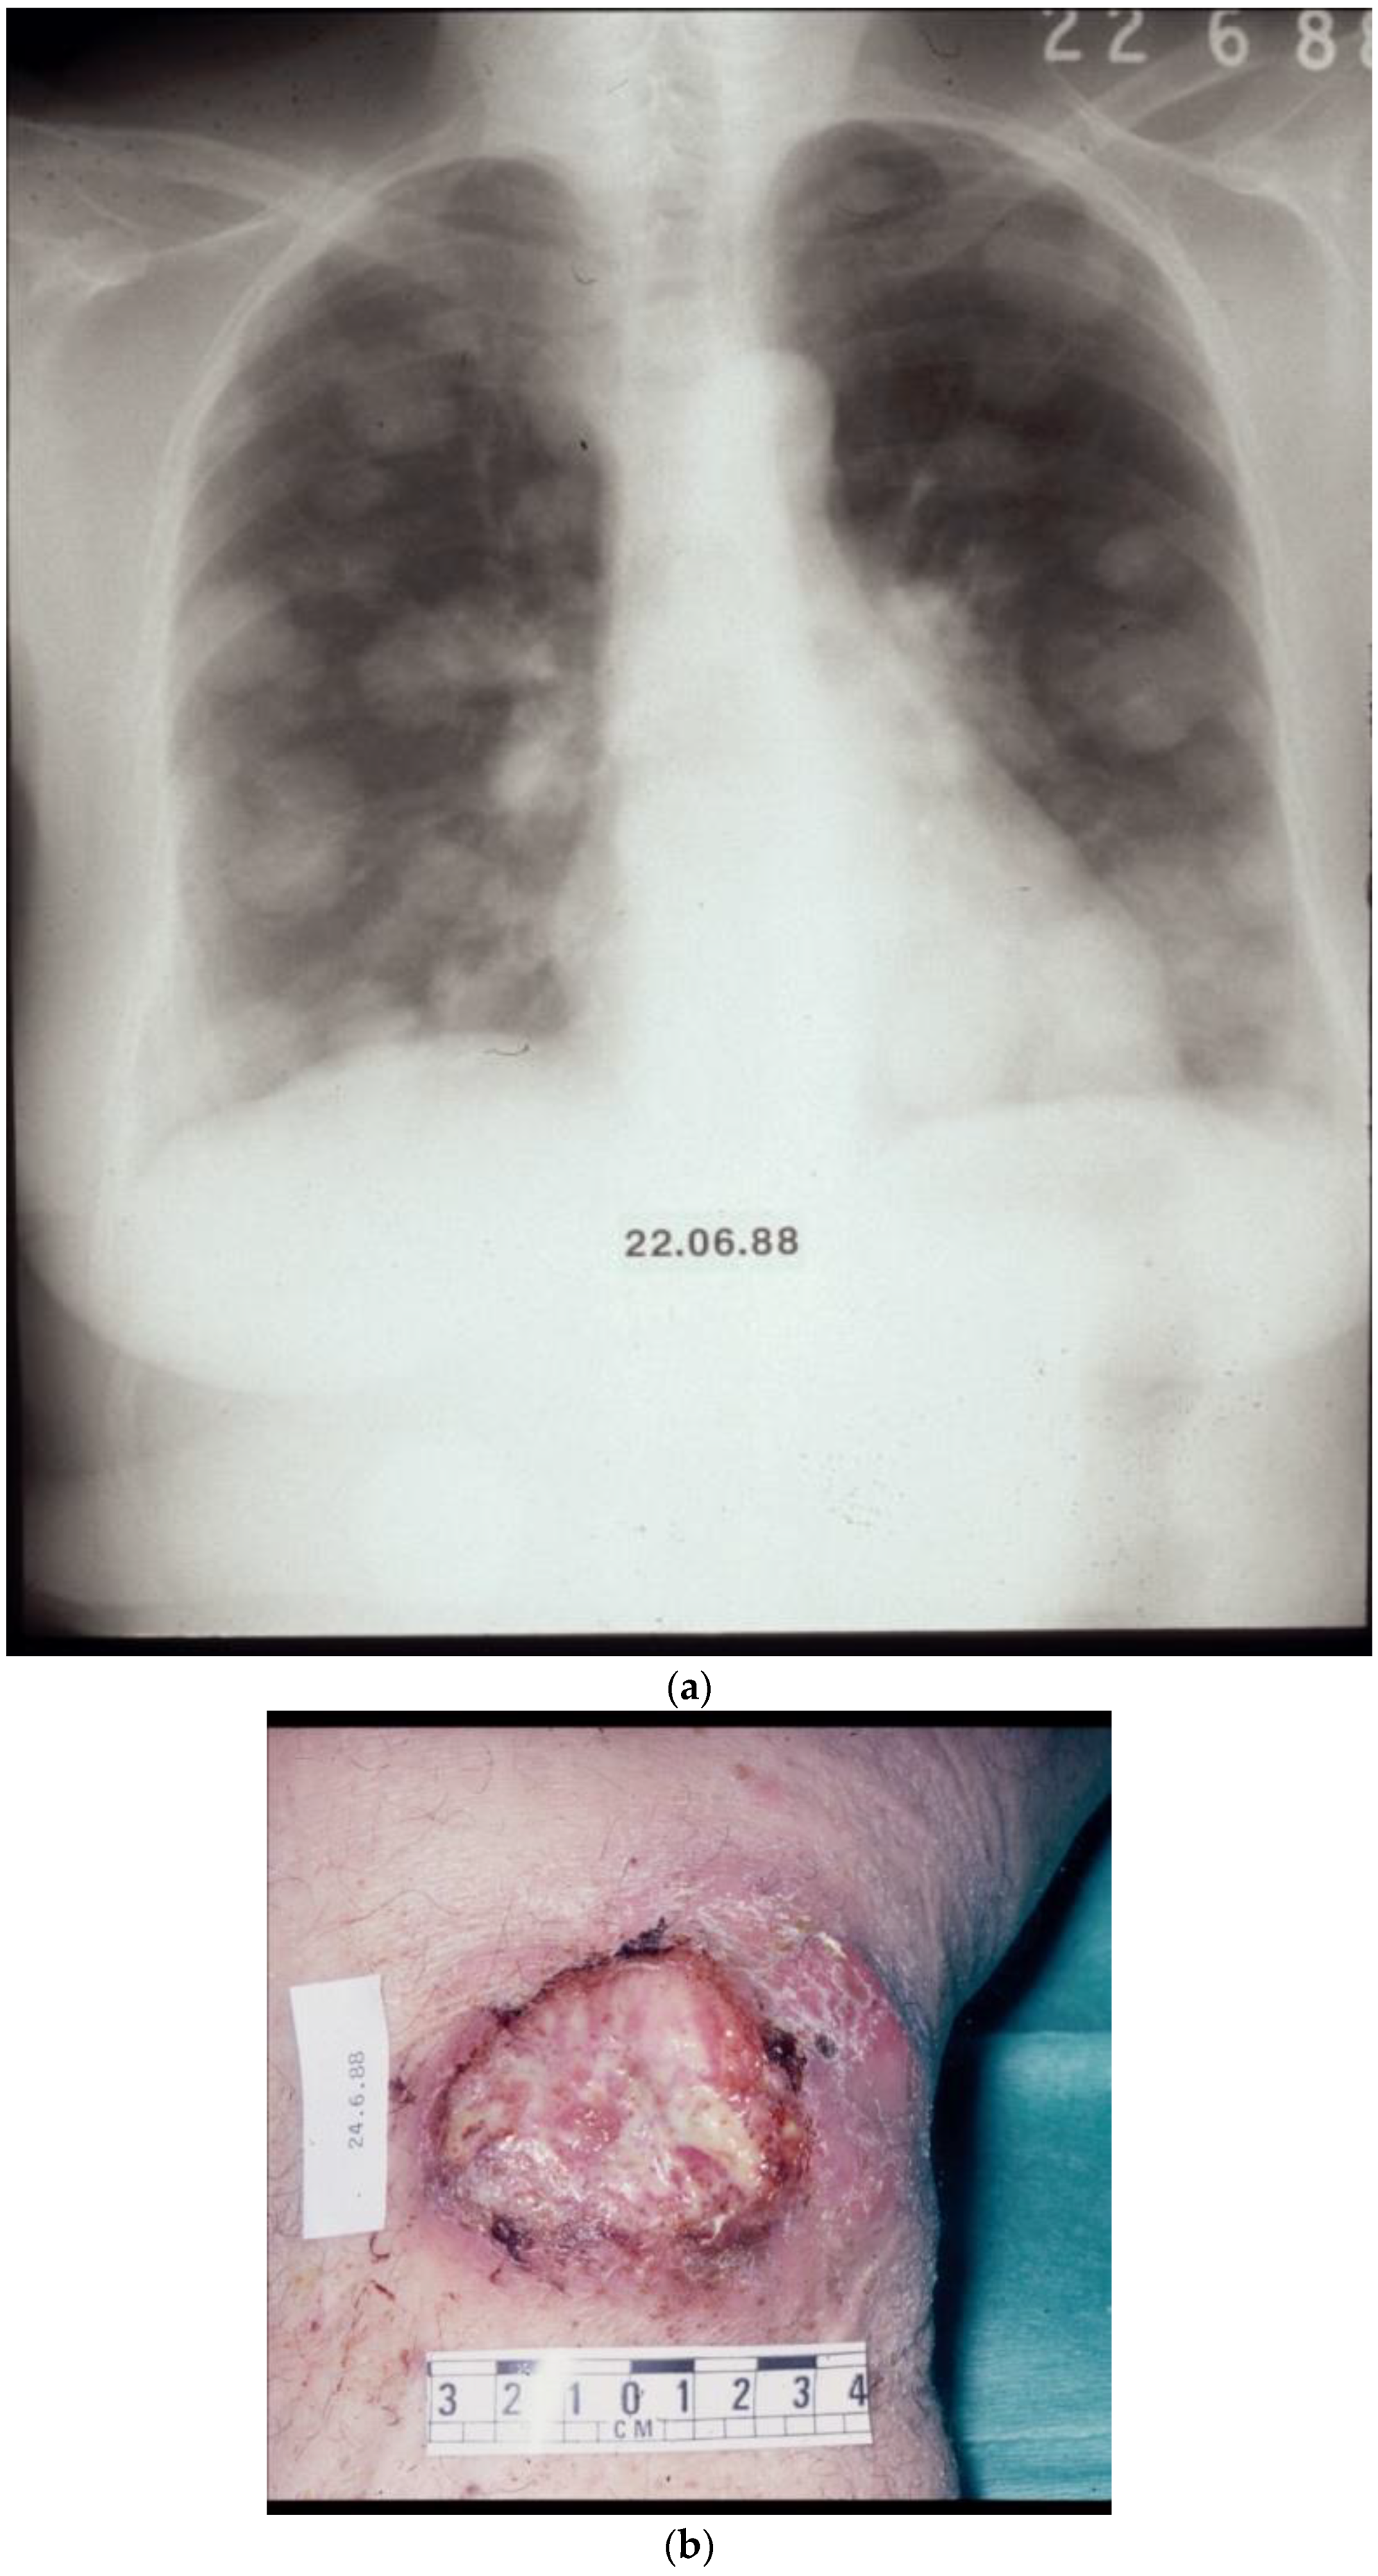

- Retsas, S.; MacRae, K.; Henry, K. Adjuvant Treatment for clinically apparent lymph node metastases (≥N1b) from melanoma: Single-institution experience from a cohort of 318 patients. Melanoma Res. 2002, 12, A15. [Google Scholar]

- Retsas, S.K. Clinical and histologic involvement of regional lymph nodes in malignant melanoma. Adjuvant vindesine improves survival. Cancer 1994, 73, 2119–2130. [Google Scholar] [CrossRef] [PubMed]